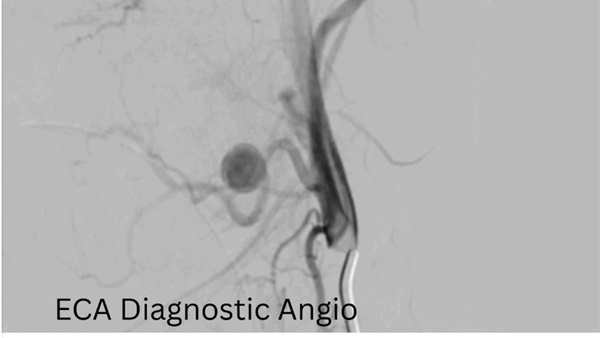

وأكد الدكتور حسان النعماني رئيس الجامعة، أن سرعة التشخيص ودقة التدخل كانتا عاملين حاسمين في إنقاذ حياة الطفلة، مشيرًا إلى أن جاهزية مستشفيات سوهاج الجامعية والتكامل بين أقسامها المختلفة أسهما في التعامل الفوري مع الحالة وفق أحدث الأساليب العلاجية. وأضاف أن فريق الأشعة التداخلية أجرى الفحوصات والأشعات اللازمة فور وصول الطفلة، والتي كشفت عن وجود تمدد شرياني نازف بأحد الشرايين الرئيسية بالرقبة في جدار الحلق، ما تطلب تدخلاً عاجلاً عالي الدقة.

ومن جانبه، ذكر الدكتور احمد كمال المدير التنفيذي للمستشفيات الجامعية، أنه تم تجهيز وحدة القسطرة على الفور، حيث نجح الفريق الطبي في غلق التمدد الشرياني باستخدام حلزونات دقيقة عبر القسطرة التداخلية، مما أسهم في السيطرة الكاملة على النزيف دون الحاجة إلى جراحة تقليدية، وتقليل احتمالات المضاعفات.

وأكد الدكتور محمد زاكي رئيس قسم الأشعة، بأن الحالة خرجت في وعي كامل مع استقرار تام في العلامات الحيوية، مؤكدًا أن هذا التدخل يمثل نموذجًا للتنسيق السريع بين الفرق الطبية في الحالات الطارئة.